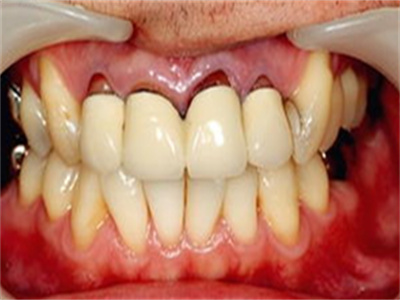

牙龈炎是发生于牙龈组织的炎症,患者可出现牙龈出血伴肿胀、发红、正常形态改变和偶尔不适等症状。本病主要由口腔卫生状况差导致,包括口腔不洁、牙菌斑等,诊断依据临床检查,治疗包括专业牙齿清洁和加强家庭口腔卫生。

牙龈炎可先引起牙齿与牙龈之间的沟(龈沟)加深,然后牙龈充血,炎症围绕一个或多个牙齿,伴牙龈乳头肿胀和易出血。一般无痛,可自行消退,也可维持轻度炎症数年。